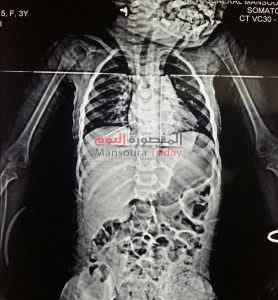

نجح فريق جراحة القلب و الصدر بمستشفى المنصورة العام الجديد فى استخراج إبرة خياطة من الرئتين و الغشاء المبطن للقلب لطفلة عمرها 3 سنوات .

وأكد الأطباء أن أهل الطفلة لم يستطيعوا تحديد سبب ماتعاني منه الطفلة رغم وجود بؤرة صديدية على جلد الطفلة ، ولكن بعد عمل الأشعات والفحوصات من قبل الفريق الطبي بمستشفى العام الجديد اتضح أنه تم اخترق الإبرة لصدر الطفلة أثناء النوم.

قام الفريق المعالج بعمل استكشاف للصدر من الجانب الأيمن و فتح الغشاء التامورى الخاص بالقلب وتم ازالة الجسم الغريب (إبرة خياطة 5 سم ) ، حيث كانت تلامس عضلة القلب من البطين الايمن مما سبب تهتك فى جدار القلب نتج عنه تجمع دموى والذي تم سحبه أثناء الجراحة، وأضاف الفريق المعالج أن الطفلة حالتها الصحية مستقرة تماما و تخضع للعلاج داخل المستشفى.